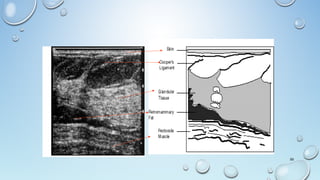

• The Subcutaneous Fat LayerSubcutaneous Fat Layer Is Demonstrated Superficially As

Hypoechoic Tissue Compared To The Glandular Tissue From Which It Is

Separated By A Well-defined Scalloped Margin.

• Normal DuctsDucts Are Often Visible, Particularly In The Subareolar Region,

As Anechoic Tubular Structures.

• Deep To The Glandular Tissue, A Retromammary Fat LayerA Retromammary Fat Layer Is Usually

Visible And, Behind This, The Structures Of The Chest WallChest Wall.

• The SubcutaneousFat LayerSubcutaneous Fat Layer Is Demonstrated Superficially As Hypoechoic Tissue Compared To The Glandular Tissue From Which It Is Separated By A Well-defined Scalloped Margin. • Normal DuctsDucts Are Often Visible, Particularly In The Subareolar Region, As Anechoic Tubular Structures. • Deep To The Glandular Tissue, A Retromammary Fat LayerA Retromammary Fat Layer Is Usually Visible And, Behind This, The Structures Of The Chest WallChest Wall. 64